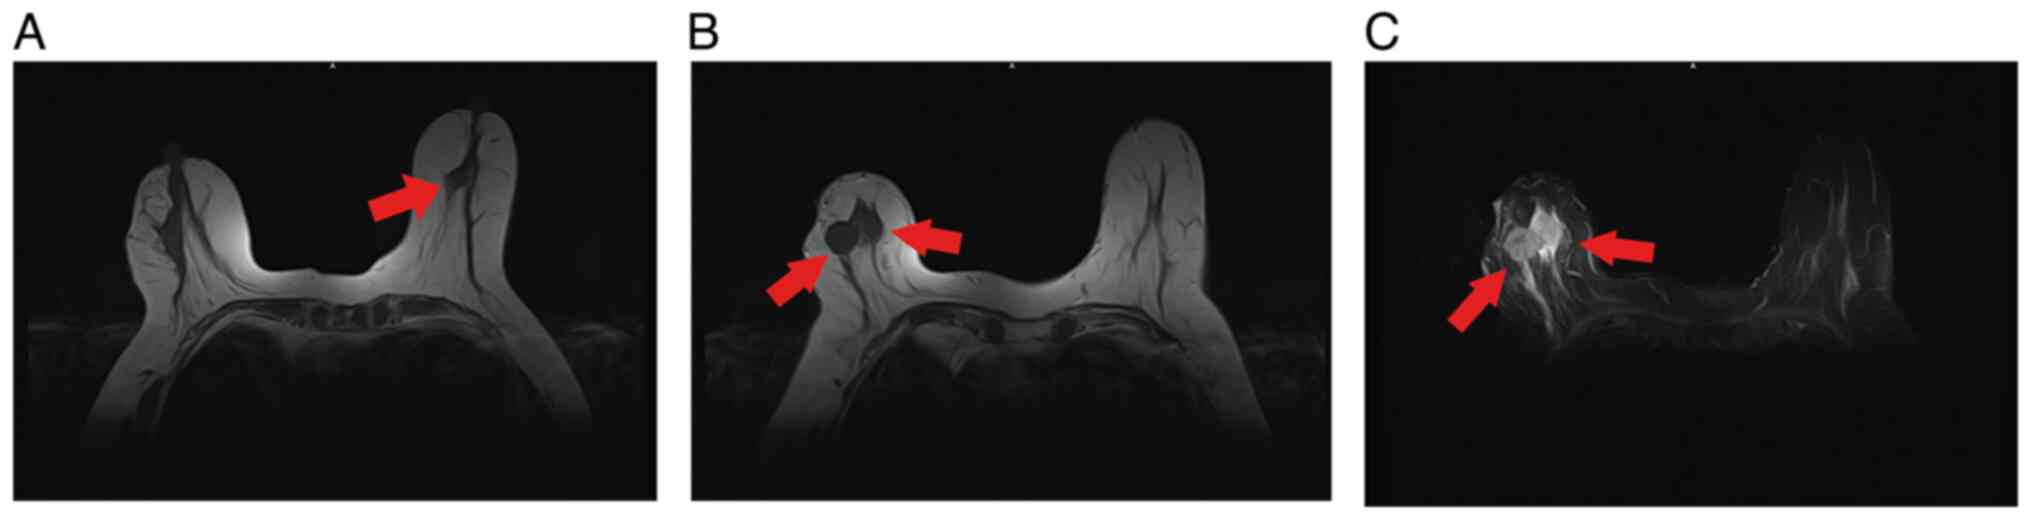

The incidence of synchronous bilateral breast cancer (SBBC) is very low, and SBBC with discordant molecular subtypes is even more uncommon. As such, little is known about the pathogenesis of SBBC with discordant molecular subtypes, and reports about this entity are scarce. In the present study, the case of a 72‑year‑old female patient who presented with SBBC with discordant molecular subtypes is reported, with a stage IA hormone receptor negative {human epidermal growth factor receptor‑2 [HER2(+)]} tumor in the left breast and a stage IIIA hormone sensitive tumor [HER2(‑)] in the right breast. Whole‑exome sequencing was performed to identify the differential genetic variations in the BBC tissues. A total of 8 key mutated cancer susceptibility genes (ALK, BRCA1, FAT1, HNF1A, KDR, PTCH1, SDHA and SETBP1) were screened, and mutations were found in 10 vital cancer driver genes, including BRCA1, EBF1, MET, NF2, NUMA1 RALGAPA1, ROBO2, SMYD4, UBR5 and ZNF844. The high‑frequency mutated genes mainly contained missense mutations, among which single nucleotide variants were the most common mutations, with C > T and C > A as the main forms. The pathways associated with the high frequency mutated genes were further elucidated by functional category and Kyoto Encyclopedia of Genes and Genomes pathway enrichment analyses. Heterogeneity in the hormone receptor and HER2 status of SBBC poses unique therapeutic challenges. Future studies should aim to identify the optimal management strategy for this disease.

Figure 1